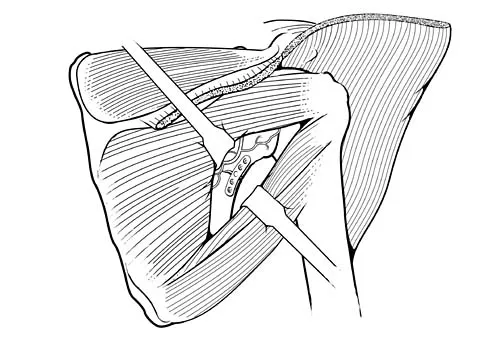

A right-handed 24-year-old professional baseball player injured his left shoulder 6 weeks ago when he dove forward and landed hard with the arm extended. He reports that the shoulder "slipped out" and "went back in." The shoulder did not need to be reduced. He now reports deep pain in the front of the shoulder when batting on either side and is hesitant to raise his left arm up over his head to catch a ball. Examination reveals no obvious deformities of the shoulder and a somewhat guarded, limited range of motion in all planes. Provocative tests for the rotator cuff and labrum are equivocal. MRI scans are shown in Figures 16a and 16b. What is the best course of action?

Explanation

A 44-year-old recreational weight lifter reports chronic deep pain in his left shoulder that is aggravated by any pressing exercises. He also notes a painful catch in the shoulder occurring with rotational movements. Physical therapy and nonsteroidal anti-inflammatory drugs for 3 months have failed to provide relief. Examination reveals pain with O'Brien's test but no signs of instability. MRI scans are shown in Figures 4a and 4b. Treatment should now consist of

Detailed Explanation